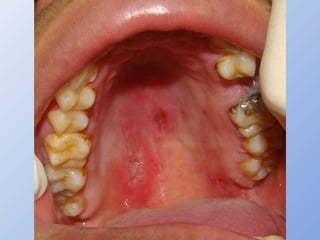

HISTOP. DISSEMINADA CRÔNICA

• Imunodepressão moderada

• Lesões mucocutâneas freqüentes

• Comp laríngeo:

– 50% dos casos

– disfonia, odinofagia, dispnéia, tosse, expectoração

• Comp cav oral e orofaringe:

– 40% dos casos

– úlceras e granulomas – dor, odinofagia, sialorréia, macroglossia

– Úlcera em língua é comum